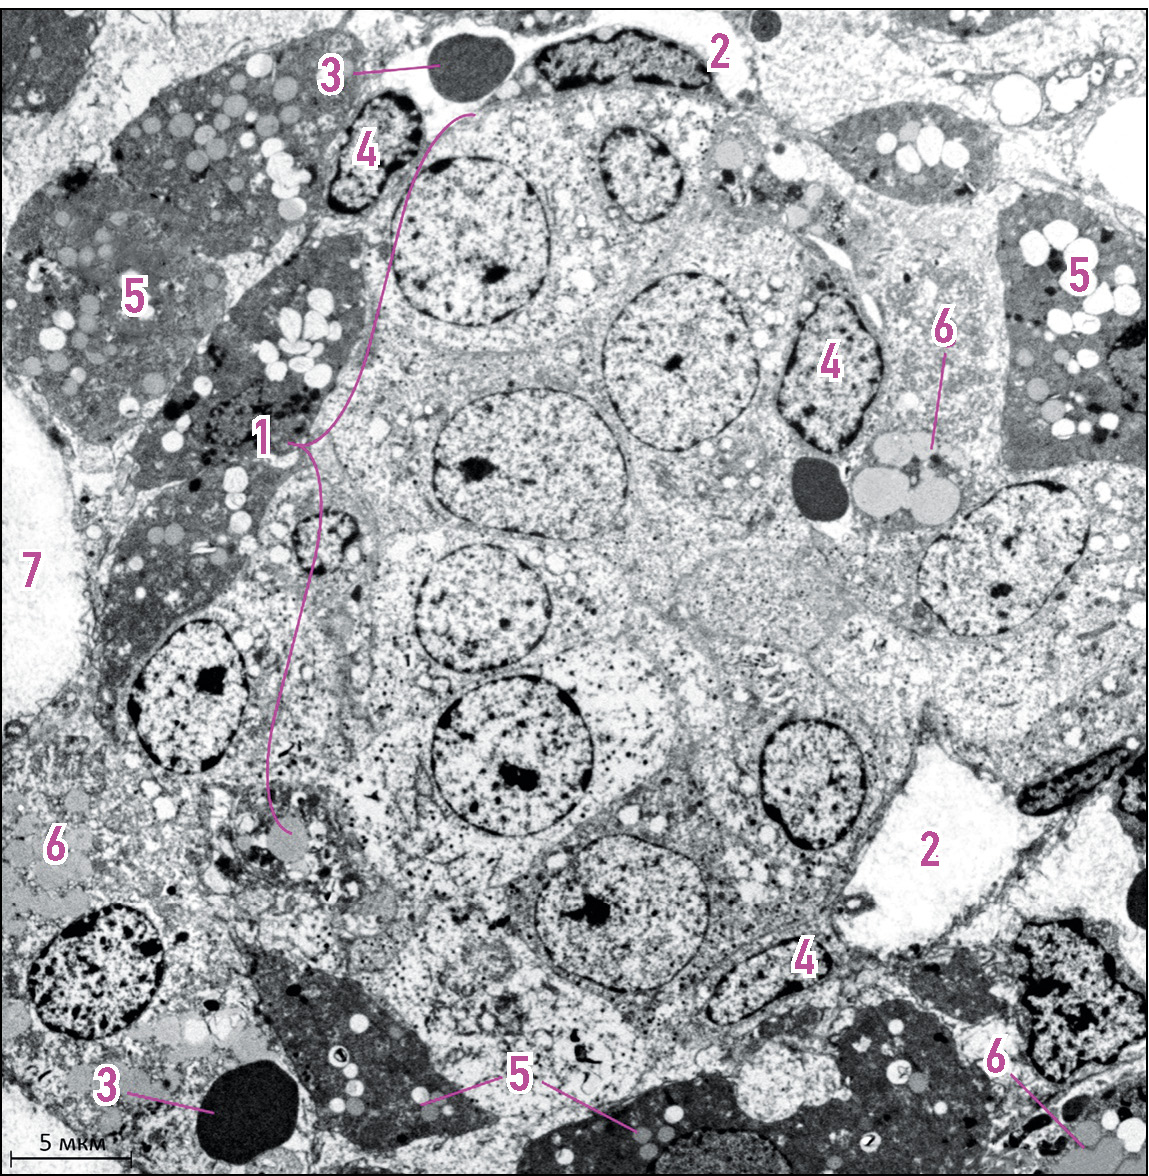

Рис. 2. Мозговое вещество надпочечника взрослой крысы: 1 — адреналин-продуцирующие модули, 2 — норадреналин-продуцирующие модули, 3 — венозные синусы, 4 — фибробласты, 5 — нервные волокна, 6 — эндотелиальная клетка, 7 — периваскулярные пространства. Трансмиссионная электронная микроскопия. © Эко-Вектор, 2024.

Fig. 2. Adrenal medulla of an adult rat: 1, A-modules; 2, NA-module; 3, venous sinuses; 4, fibroblasts; 5, nerve fibers; 6, endothelial cell; 7, perivascular spaces. Transmission electron microscopy. © Eco-Vector, 2024.